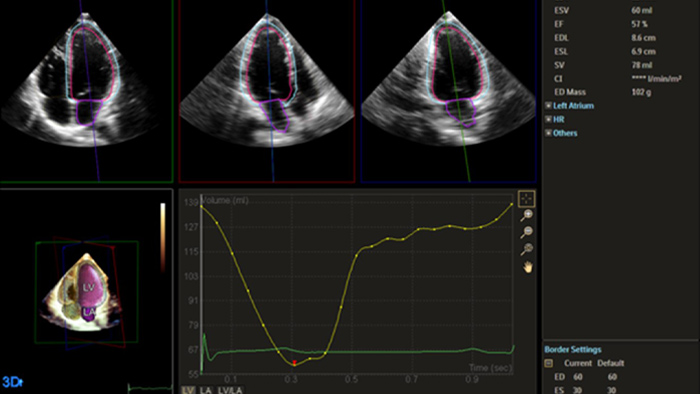

Quantification through Dynamic HeartModel.

Heart failure is prevalent worldwide, and accurate assessment of heart function using echocardiography is essential.1,2 Incorporating strain and 3D assessment of the LV and RV has historically been challenging and required specialized skill sets.

Solution Philips IntelliSpace Cardiovascular multimodality image and information management solution offers a complete look at a patient’s cardiac history. The AI-enabled automation of Philips EPIQ CVx cardiovascular ultrasound system and Philips TOMTEC -ARENA quantification tools provides efficiency and reproducibility during echocardiography studies.

Philips solutions allow for advanced quantification and analysis, with access to information anywhere, anytime across the enterprise. AI-enabled, automated tools for visualization, analysis and streamlined reporting offer robust, reproducible results to help make the effective management of heart failure a reality.